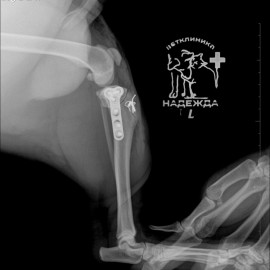

После проведённых исследований был поставлен диагноз: пателлярный вывих левого коленного сустава, разрыв передней крестообразной связки левого коленного сустава.

Была проведена операция: TPLO, трохлеопластика с рецессией блока левого бедра, дупликатура капсулы левого коленного сустава, латеральная транспозиция шероховатости левой большеберцовой кости.